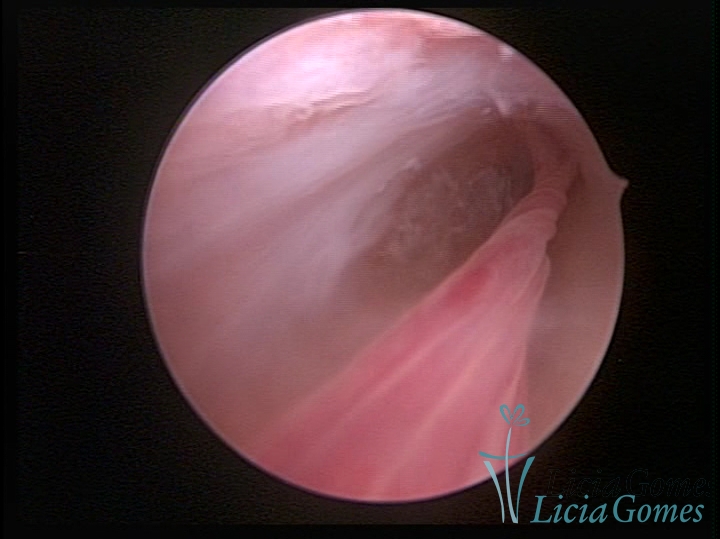

PÓLIPOS ENDOCERVICAIS

São tumores benignos, resultantes da proliferação focal reativa aos processos inflamatórios ou à situações de hiperestrogenismo, e podem ter sésseis (com a base de implantação larga) ou pediculados do epitélio.